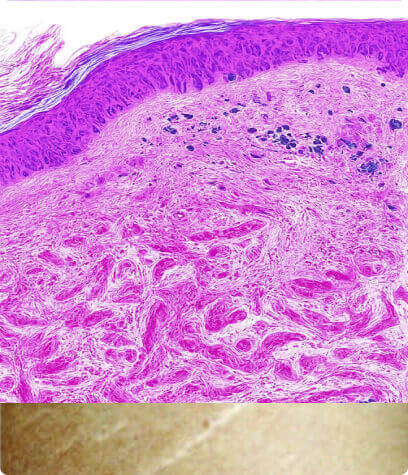

Normal Skin

Smooth and elastic with intact collagen and elastin fibers maintaining firmness and structure.

Striae Rubrae

Smooth and elastic with intact collagen and elastin fibers maintaining firmness and structure.

Striae Albae

Mature white stretch marks where collagen remodeling leads to thinning and loss of pigmentation.

How it works

- Promotes removal of damaged collagen

- Induces keratinocytes proliferation that releases growth factors to promote collagen deposition by the fibroblasts and elastin deposition

- Modulates the expression of several genes in the skin (vascular endothelial growth factor, fibroblast growth factor, epidermal growth factor, collagen type I and III) that promote extracellular matrix remodeling

This aging process is accompanied by structural and functional changes in extracellular matrix components such as collagen and elastin. The result in the appearance of fine lines and wrinkles.